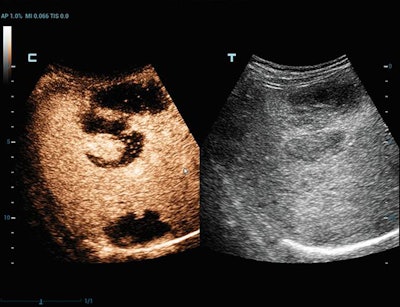

Siemens Healthineers is highlighting the Acuson Sequoia and Juniper scanners. Acuson Sequoia features a deep abdominal transducer, a 1.2-3.5-MHz ultrasound probe that produces penetration of up to 40 cm. It also boasts the company's BioAcoustic technology, which improves contrast-enhanced ultrasound (CEUS) bubble longevity, allowing for longer view time of contrast agents.

Sound Touch uses Ultra Wide Beam Tracking technology, which produces quantification metrics and visual displays of tissue stiffness. Ultra-Wideband Non-Linear (UWN+) contrast-enhanced imaging uses harmonic and fundamental signals to boost contrast and temporal resolution, while its iFusion tool supports the synthesis of routine B-mode images as well as fusion in CEUS and color/power modes. Mindray's V-flow displays hemodynamic information via speckle-tracking data taken from three plane waves.

SuperSonic Imagine is promoting Aixplorer Mach 30, which includes the company's UltraFast imaging technique to optimize conventional B-mode imaging, as well as its SWE Plus shear-wave elastography software, which helps clinicians visualize anatomical images in real-time while also superimposing color mapping of tissue stiffness. The scanner features SonicPad, a touch pad designed to reduce user fatigue, as well as a variety of transducers, including a high-frequency abdominal probe.